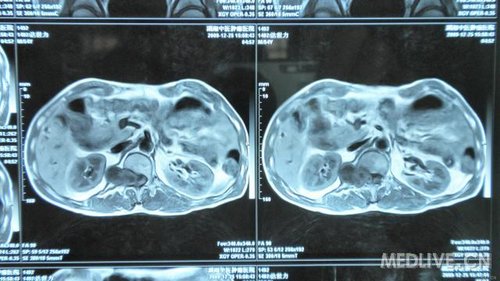

http://webres.medlive.cn/upload/000/030/212

还有CT片